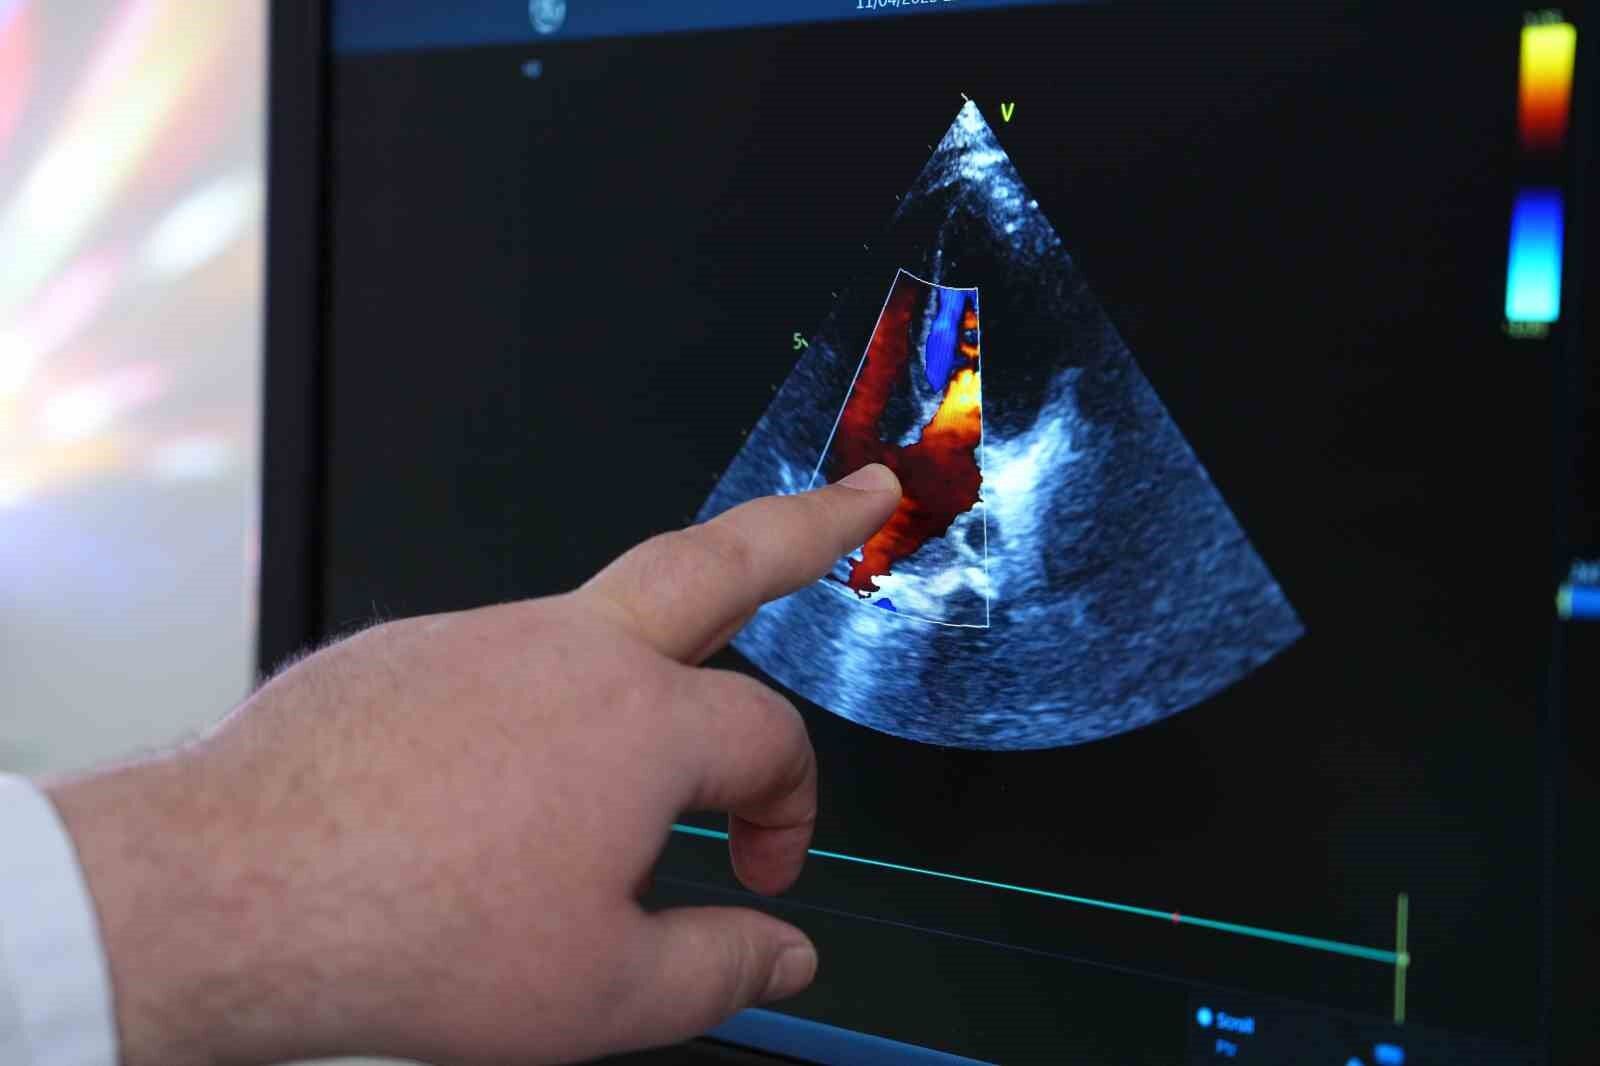

Hipertansiyonun çocukluk çağında genellikle geç fark edildiğini dile getiren Prof. Dr. Zeybek, "Ülkemizde çocuklarda rutin tansiyon ölçme alışkanlığı bulunmuyor. Bu nedenle özellikle kardiyoloji takibi olmayan çocuklarda hipertansiyon kolay kolay fark edilmiyor. Ancak ergenlik döneminde ölçümlerle birlikte tanı konulabiliyor" dedi. Çocuklarda hipertansiyonun erişkinlere kıyasla daha çok yapısal nedenlere dayandığını vurgulayan Prof. Dr. Zeybek, "Erişkinlerde obezite, diyabet, sigara gibi faktörler öne çıkarken, çocuklarda böbrek, böbrek üstü bezi, kalp ve endokrin sistemle ilgili problemler hipertansiyona neden olabiliyor. Bu nedenle tanı ve tedavi daha kapsamlı bir yaklaşım gerektiriyor" diye konuştu.

Çocuklarda kan basıncı değerlendirmesinin yaşa, kiloya ve boyuta göre farklılık gösterdiğini belirten Prof. Dr. Zeybek, "Erişkinde 140/90mmHg’nin üzeri hipertansiyon sayılırken, çocuklarda her yaş grubuna özel tansiyon aralıkları var. Bu yüzden her yaşa özel değerlendirme yapılmalı. Çocuk endokrinolojisi, çocuk nefrolojisi, kardiyoloji, diyetisyen gibi farklı branşların ortak takibiyle hipertansiyon kontrol altına alınabiliyor. Öncelikle altta yatan nedenin tespit edilip o nedene yönelik tedavi planlanmalı" dedi.